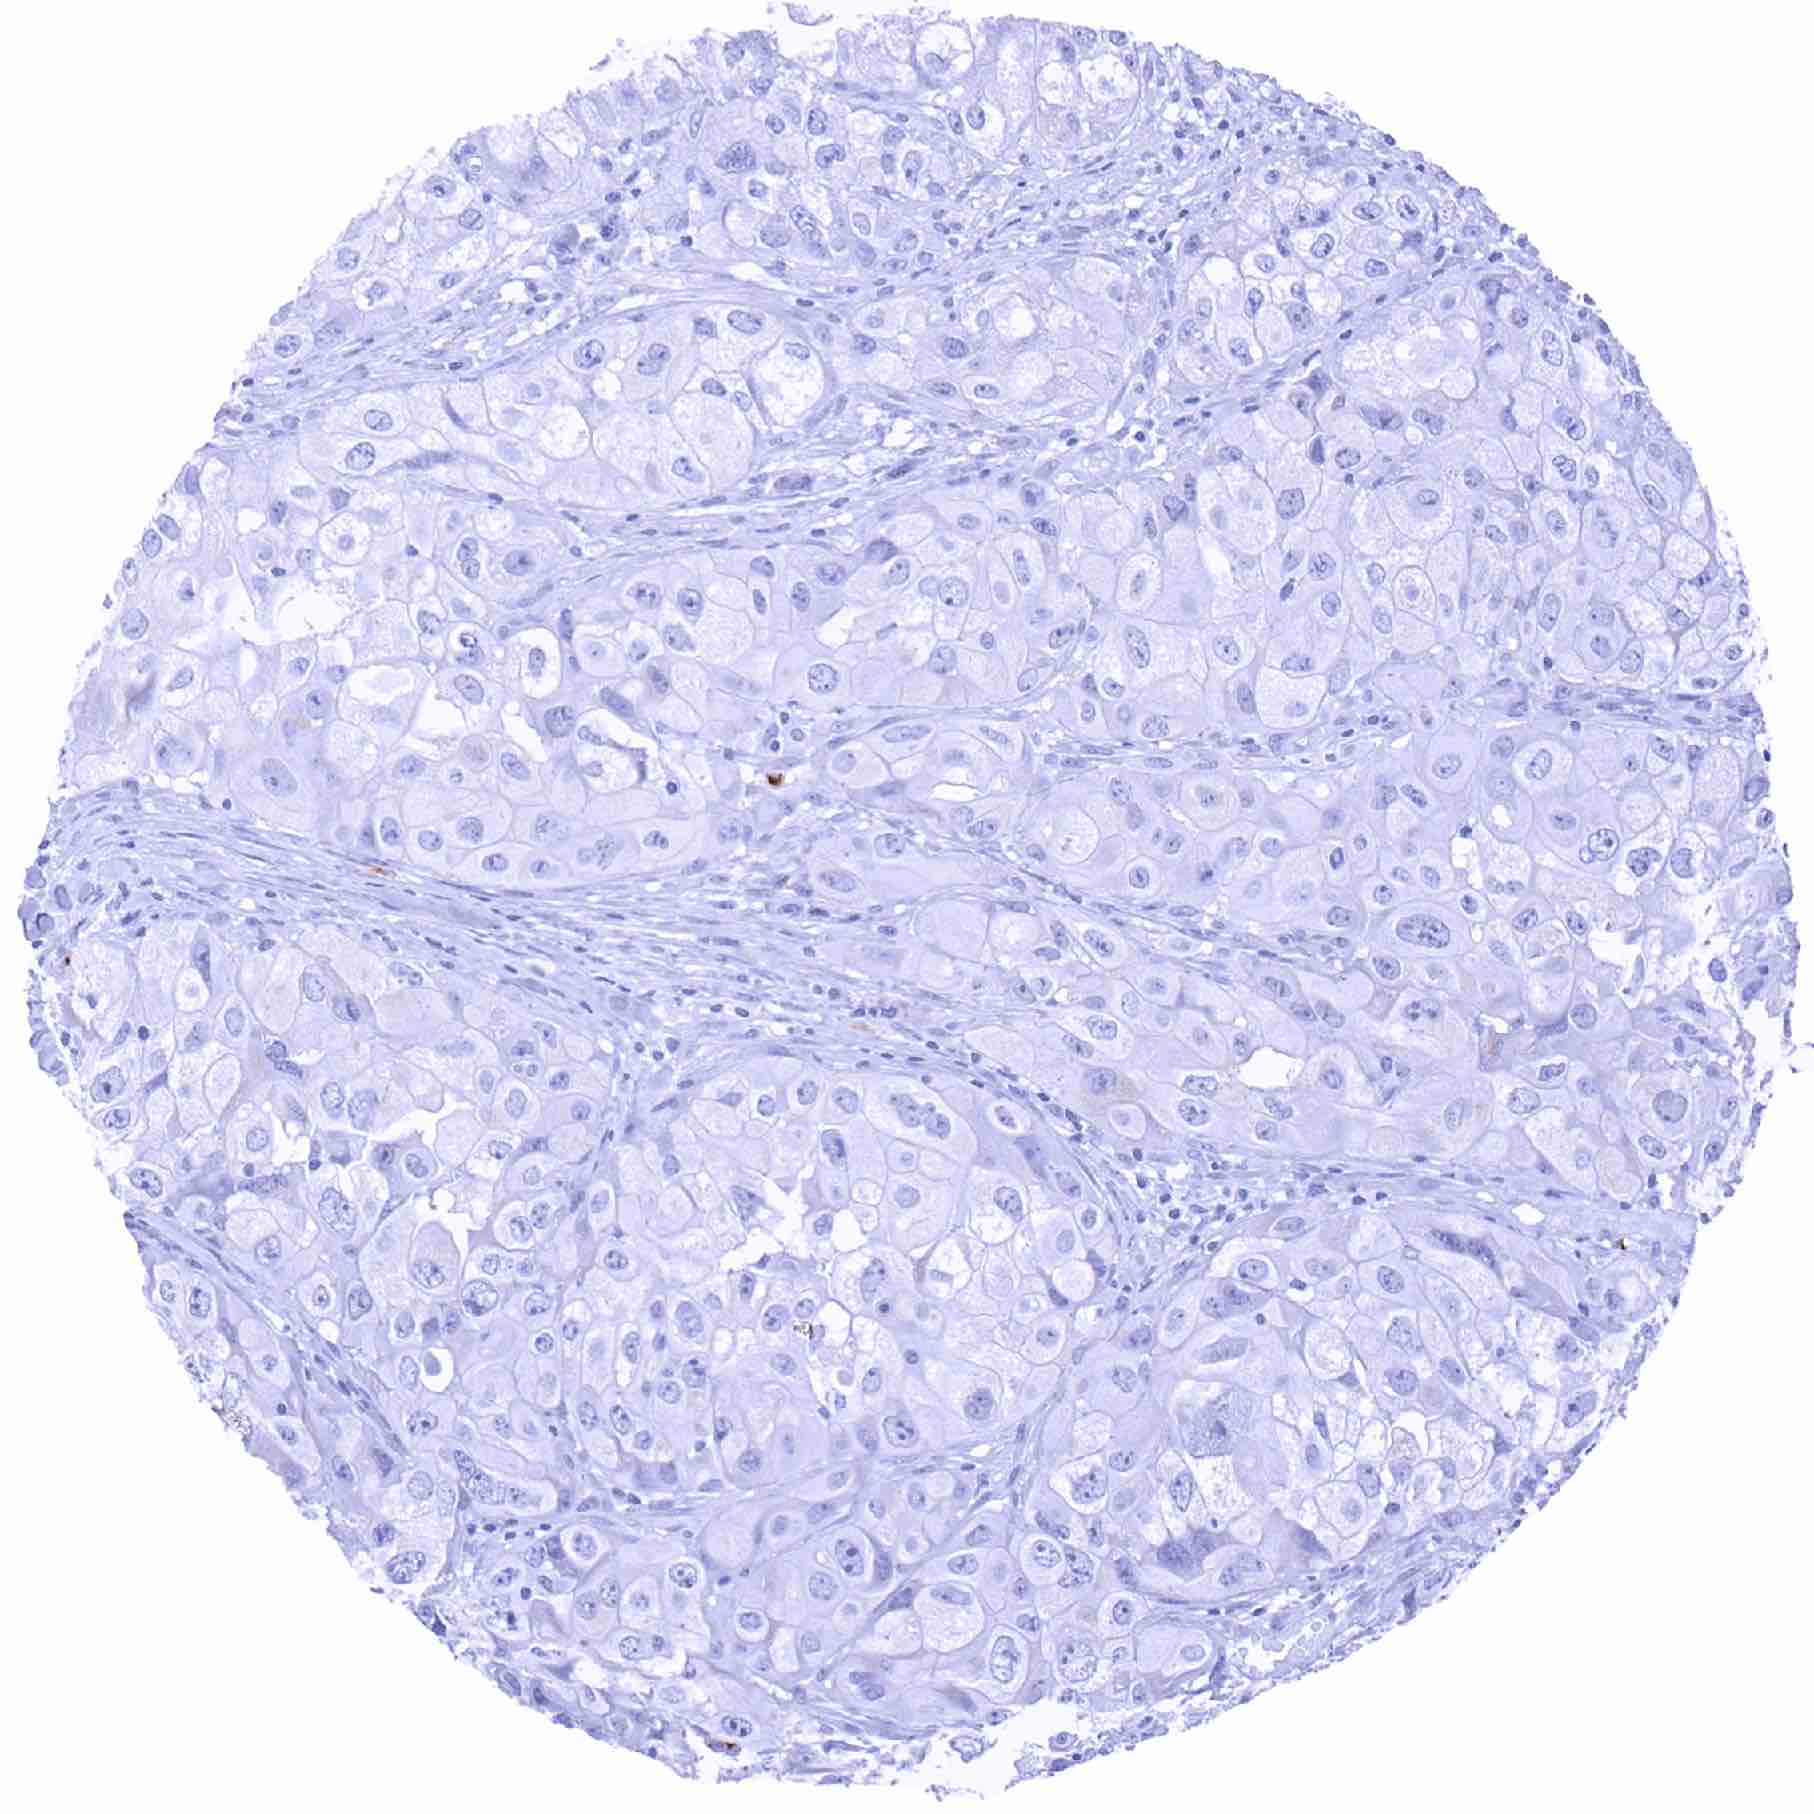

Urinary bladder – Prostein negative muscle-invasive urothelial carcinoma